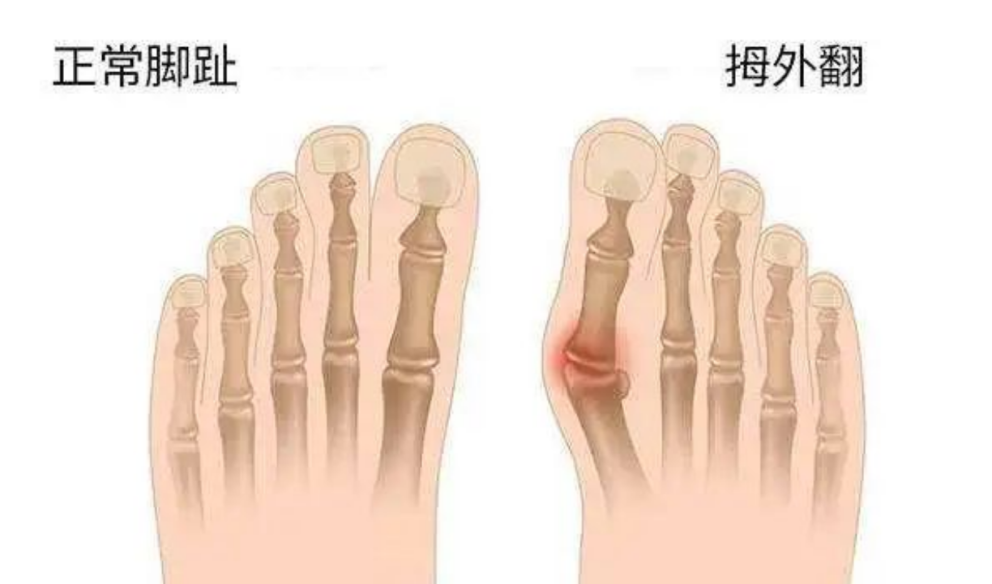

拇外翻,俗称大脚骨,多发于女性,是大脚趾向外明显倾斜,超过正常生理范围的一种足部畸形,常常伴随红肿、疼痛等症状。

正常人足的第一足趾轴线,与足的第一跖骨轴线,两者之间的夹角在0~15度之间。如果超过15度,就是拇外翻了。

具体表现为:

大拇趾关节内侧突起,表面红肿,按压有疼痛感,穿鞋挤压后明显。

大拇趾外翻,不断挤压第二趾。